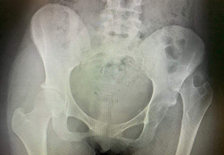

Imaging

AP and lateral X-ray of the hip and a full-length femur film are needed to exclude associated injuries. Disruption of Shenton’s line, loss of joint congruence,and a difference in femur head shape are indirect signs of an injury.

In non-displaced cases, the fracture may be occult and not visible on X-rays.MRI is the gold standard for occult fractures.If this cannot be arranged within 24 hours, a CT scan is the next best choice.In hip dislocations, CT scans help visualise associated fractures of the acetabulum, femur head or neck, and exclude loose bodies in the joint.